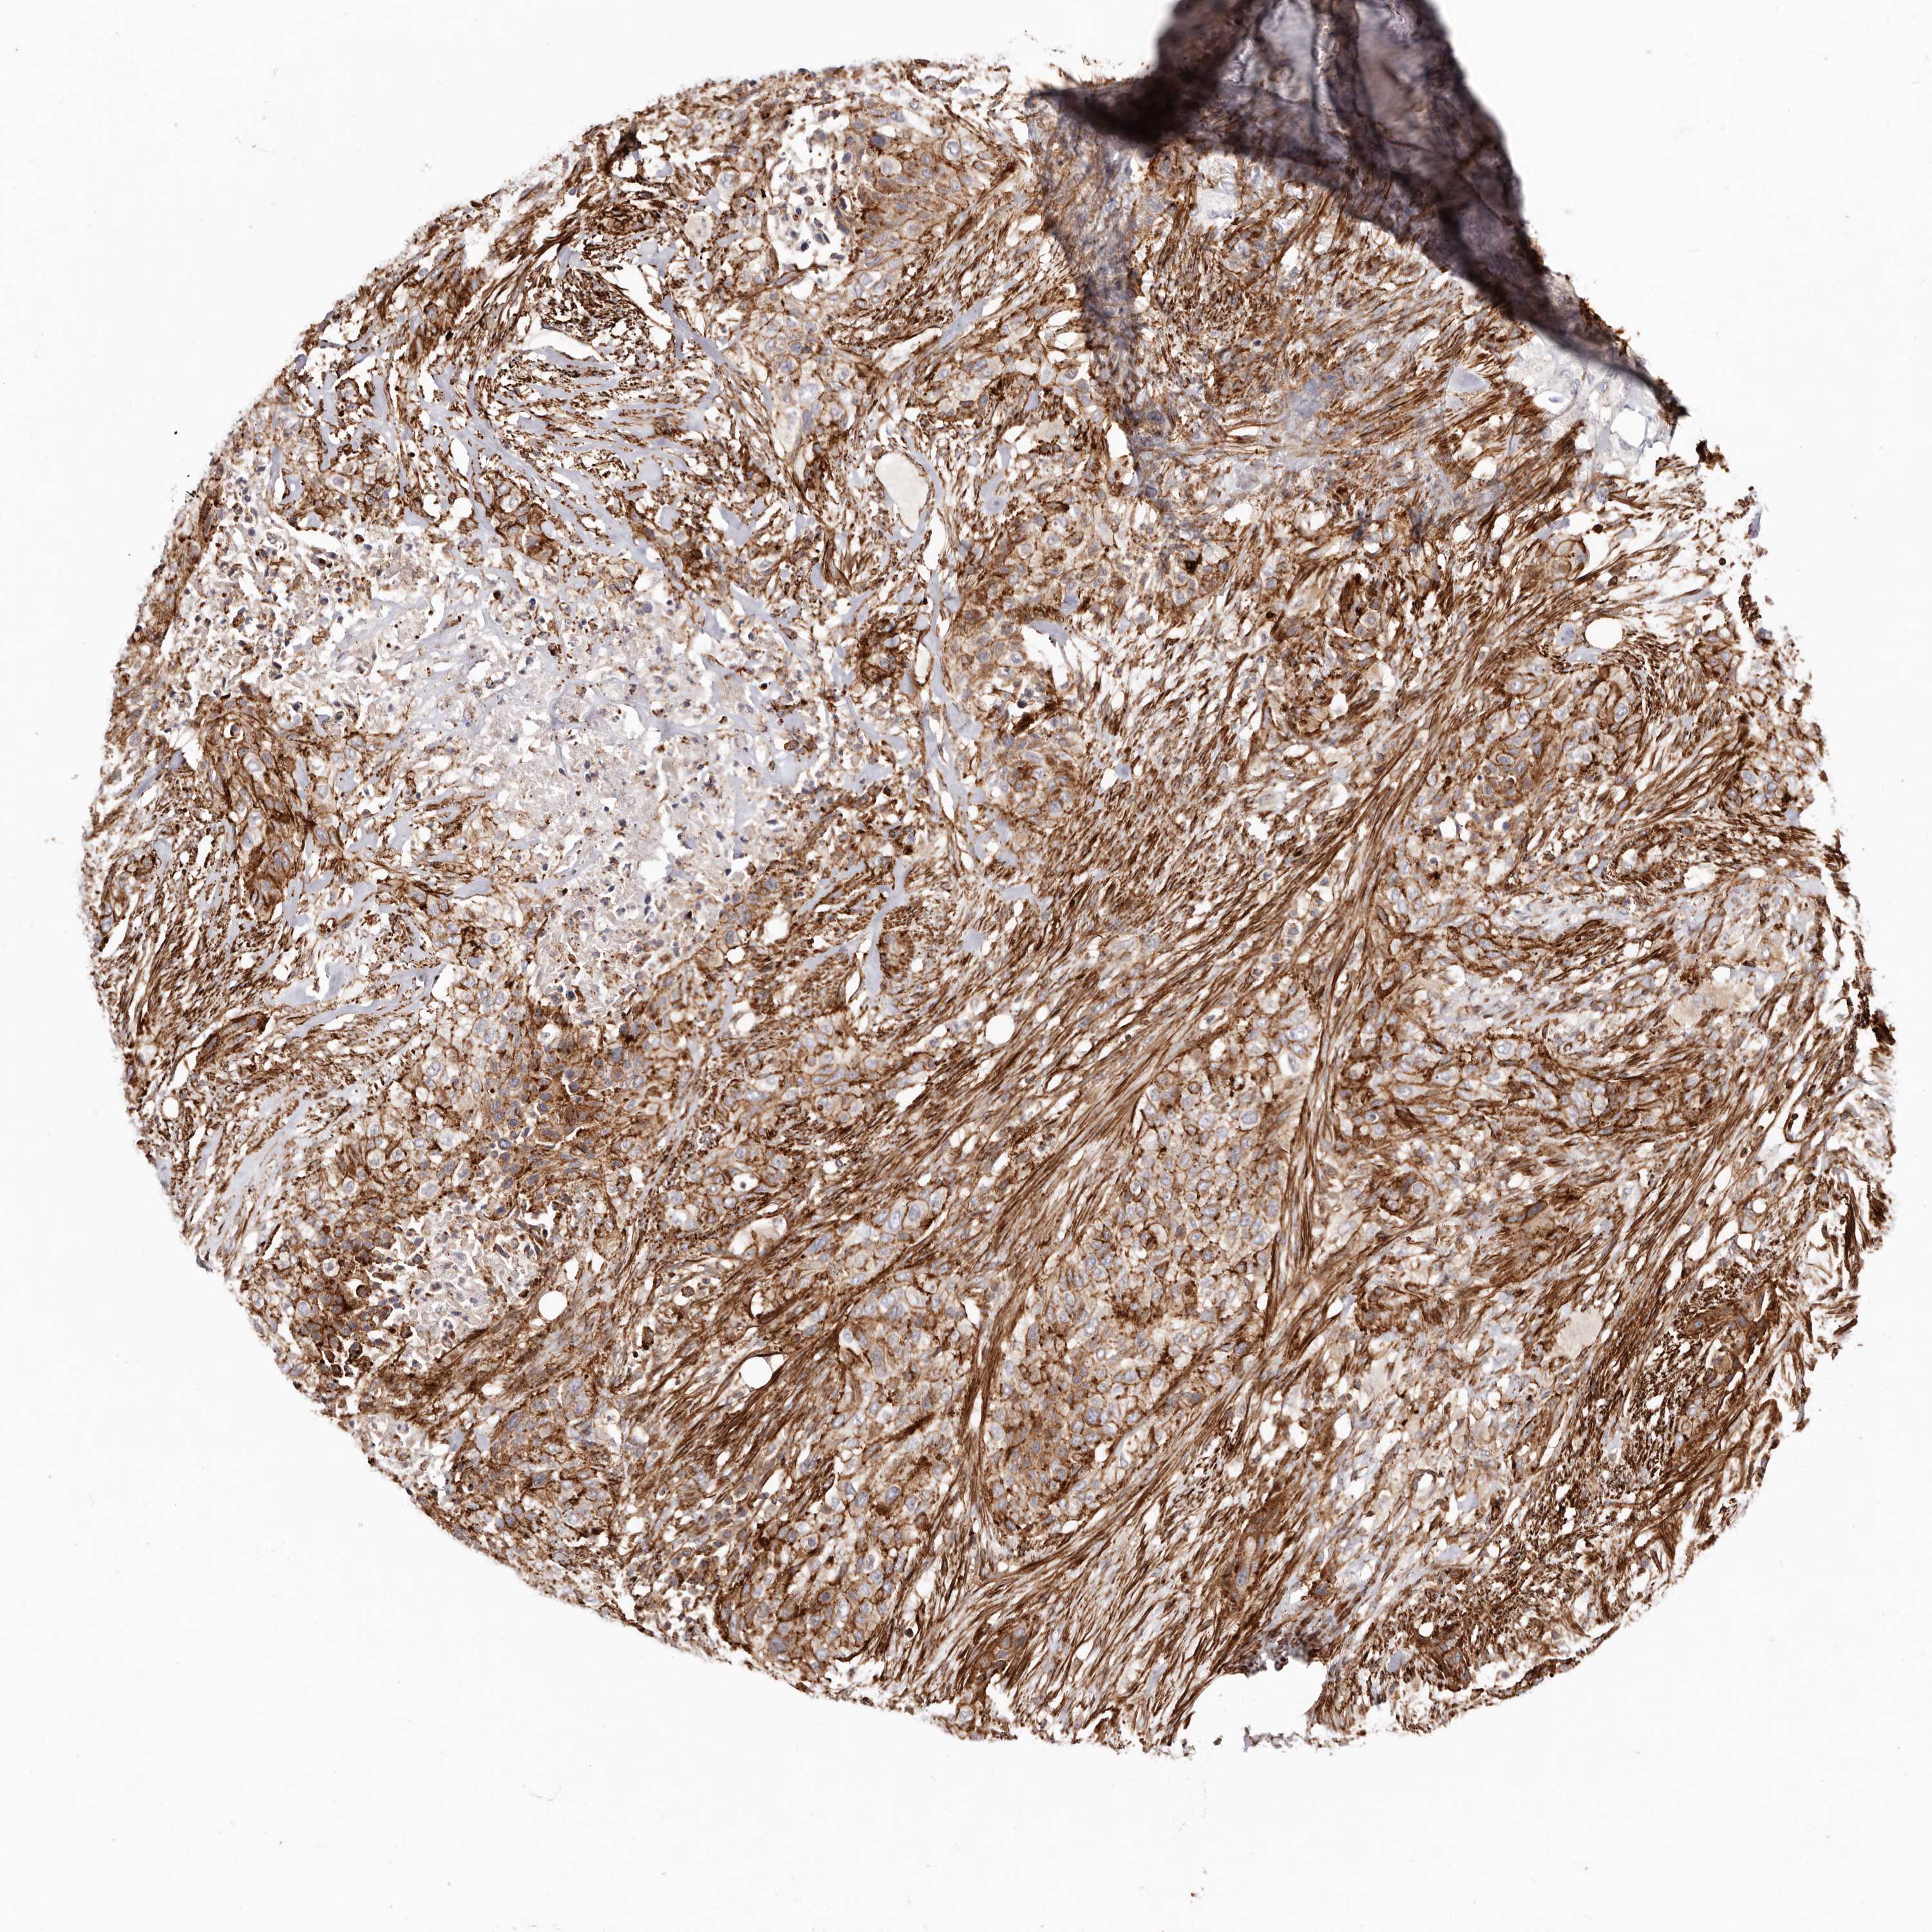

UROTHELIAL CANCER - Protein expressioni

A mouse-over function shows sample information and annotation data. Click on an image to view it in a full screen mode. Samples can be filtered based on level of antibody staining by selecting one or several of the following categories: high, medium, low and not detected. The assay and annotation is described here.

Note that samples used for immunohistochemistry by the Human Protein Atlas do not correspond to samples in the TCGA dataset.

Antibody stainingi

Antibody staining in the annotated cell types in the current human tissue is reported as not detected, low, medium, or high, based on conventional immunohistochemistry profiling in selected tissues. This score is based on the combination of the staining intensity and fraction of stained cells.

Each image is clickable and will lead to virtual microscopy that enables deeper exploration of all samples and also displays staining intensity scores, fraction scores and subcellular localization as well as patient and tissue information for each sample.

Antibody HPA004912

Antibody HPA013350

Antibody CAB012209

Urothelial carcinoma, Low grade

Urothelial carcinoma, High grade